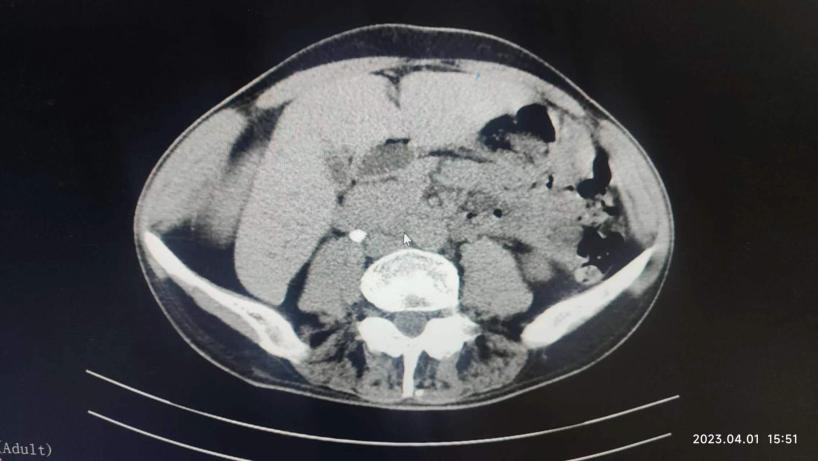

原来冉先生曾在六年前也患过一次肾结石,由于他从小患有强直性脊柱炎,脊柱生理结构与普通人不同,手术难度、麻醉难度与普通结石患者完全不在同一个级别上。当时他辗转找到刘主任,为他成功完成了微创碎石手术。

六年后,冉先生再次患者上双肾结石+左侧输尿管结石,他毫不犹豫地再次找到刘洪春主任。在刘洪春主任带领的泌尿外科团队的精心安排下,制定了“输尿管软镜+摩西钬激光碎石术”两期手术的方案,采用局部麻醉方式分期进行。